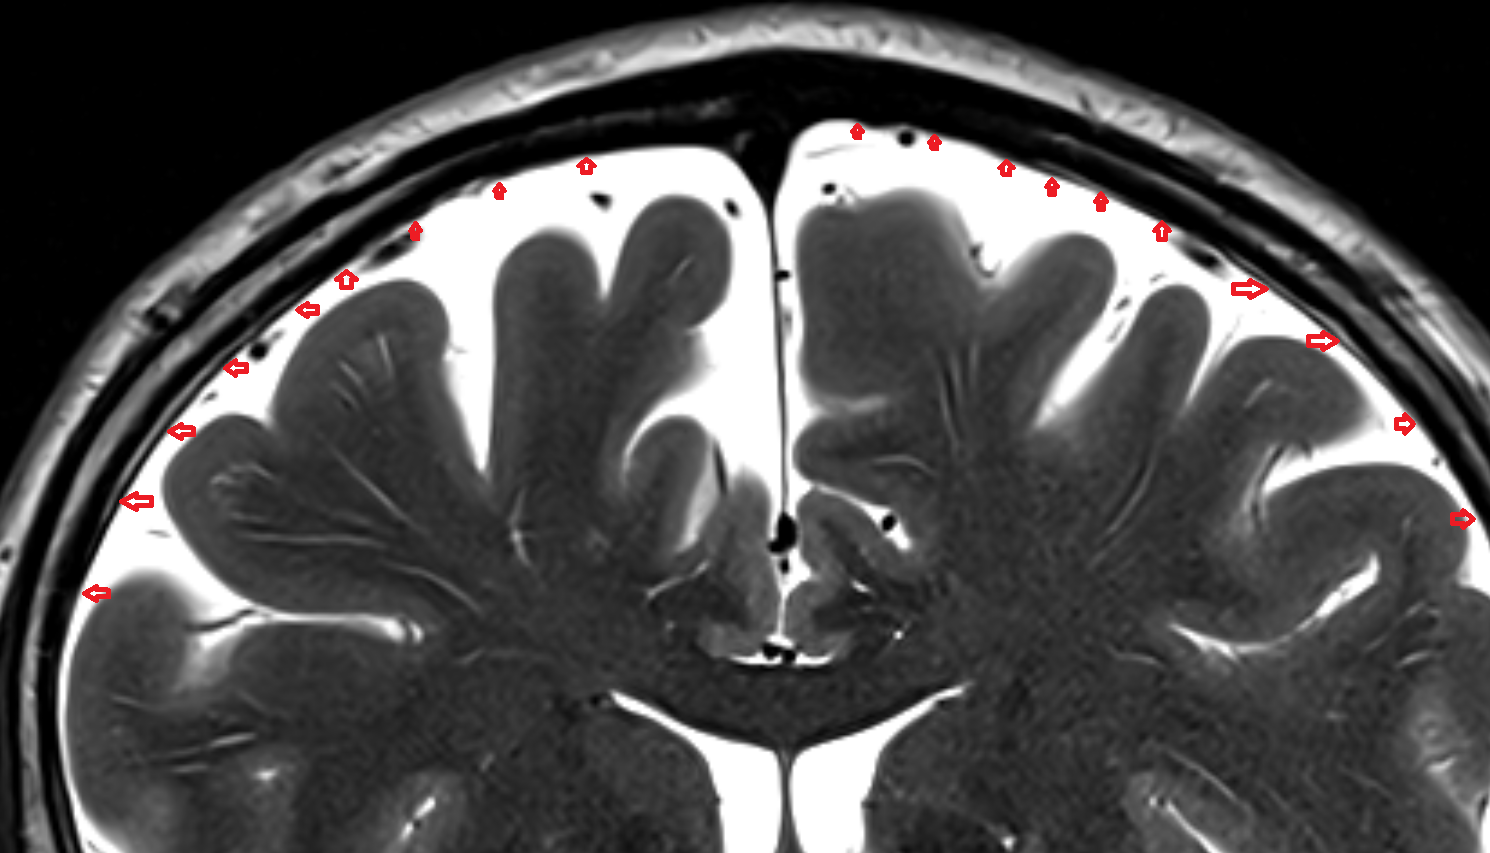

- Fetal brain

- Fetal caudate nucleus

- Fetal thalamus

- Fetal cerebellum

- Fetal occipital lobe

- Fetal temporal lobe

- Fetal parietal lobe

- Fetal frontal lobe

- Fetal third ventricle

- Fetal fourth ventricle

- Fetal lateral ventricle